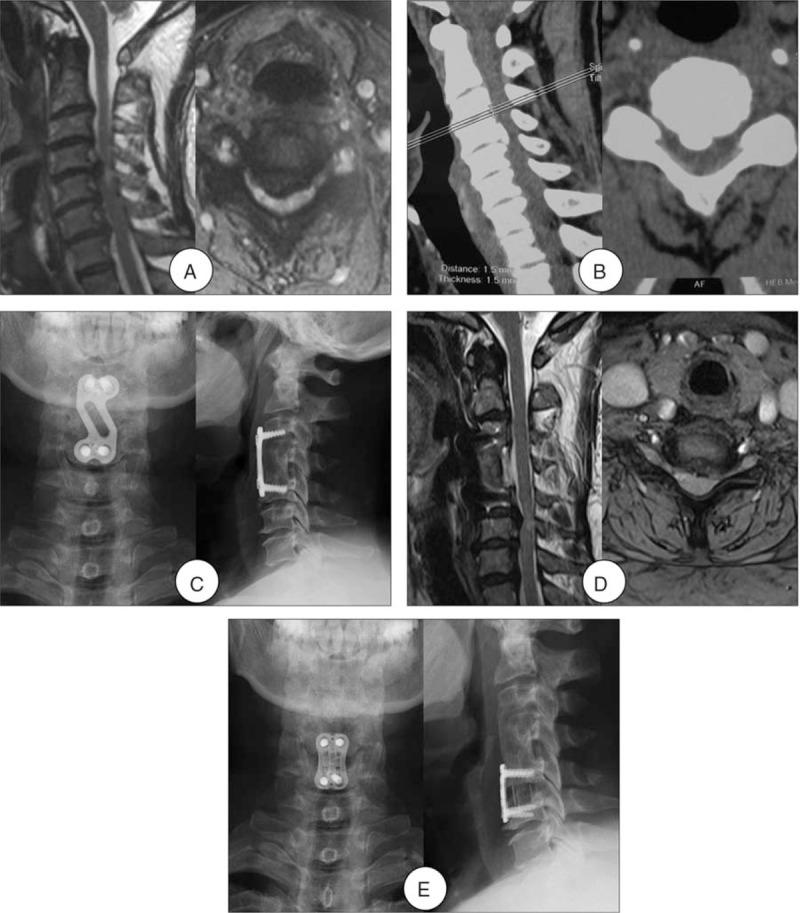

Studies in the literature have not delineated the surgical approaches of symptomatic adjacent segment diseases (ASDs) in patients undergoing reoperation after an initial anterior cervical fusion (ACF). The purpose of this study was to determine the optimal surgical approaches of ASD and the incidence of the dysphagia after reoperation.This was a retrospective study of 49 patients with ASD after an initial ACF surgery, which had undergone a reoperation at our medical center between January 2010 and December 2014. The surgical approaches were used by anterior cervical discectomy and fusion (ACDF), ACDF with the Zero-profile device, laminoplasty, and laminectomy with internal fixation. Patients were classified according to the different surgical approaches of anterior (n = 38) versus posterior (n = 11) groups and ACDF (n = 25) versus Zero-P (n = 13) groups. Clinical evaluations were performed preoperatively and repeated in 24 months after operation.This retrospective study included 26 men and 23 women with a mean age at revision surgery of 54.3 years and ASD onset time of 7.3 years. The patients were followed up with an average of 4.1 years. The reoperation rate was 5.4% in this study. The Japanese Orthopaedic Association (JOA), Neck Disability Index (NDI), and visual analogue scale (VAS) scores demonstrated significant improvements compared with preoperative in both anterior and posterior groups (P < .05). However, there were no differences between the 2 groups (P > .05). The operation time of ACDF group was more than Zero-P group, with significant differences (P < .05). However, there were no differences in JOA, NDI, and VAS scores between the ACDF and Zero-P groups pre- and postoperative (P > .05). A total of 12 (24.5%) patients had dysphagia after reoperation. The incidence of dysphagia in Zero-P group (1/13) was less than ACDF group (11/25), with significant differences (P < .05). There were no cases of major neurological or vascular complications, and wound complications.The clinical situation, initial operation, and secondary preoperative imaging findings were analyzed comprehensively, anterior or posterior approach were chosen, which can effectively relieve spinal cord compression and improve spinal cord function. In ACDF with the Zero-profile device surgery, there was no need to remove the previous internal fixation, shorten the operation time, and reduce the incidence of postoperative dysphagia.

这是一项对49例初次ACF手术后发生ASD且于2010年1月至2014年12月在我们医疗中心接受再次手术患者的回顾性研究。手术入路包括颈椎前路椎间盘切除融合术(ACDF)、使用Zero-profile装置的ACDF、椎板成形术以及椎板切除内固定术。患者根据前路(n = 38)与后路(n = 11)组以及ACDF(n = 25)与Zero-P(n = 13)组的不同手术入路进行分类。术前进行临床评估,并在术后24个月重复评估。

这项回顾性研究包括26名男性和23名女性,再次手术时的平均年龄为54.3岁,ASD发病时间为7.3年。患者平均随访4.1年。本研究中的再次手术率为5.4%。日本骨科协会(JOA)、颈部功能障碍指数(NDI)和视觉模拟量表(VAS)评分显示,前后两组与术前相比均有显著改善(P <.05)。然而,两组之间无差异(P >.05)。ACDF组的手术时间比Zero-P组长,差异有统计学意义(P <.05)。然而,ACDF组和Zero-P组术前和术后的JOA、NDI和VAS评分无差异(P >.05)。共有12例(24.5%)患者再次手术后出现吞咽困难。Zero-P组(1/13)吞咽困难的发生率低于ACDF组(11/25),差异有统计学意义(P <.05)。未发生重大神经或血管并发症以及伤口并发症。

综合分析临床情况、初次手术及二次术前影像学表现,选择前路或后路手术入路,可有效解除脊髓压迫并改善脊髓功能。在使用Zero-profile装置的ACDF手术中,无需拆除先前的内固定,缩短了手术时间,并降低了术后吞咽困难的发生率。